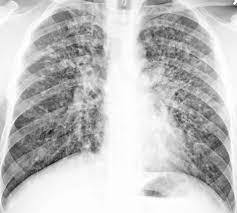

Honeycomb lung appearance. Characteristic of interstitial lung disease.